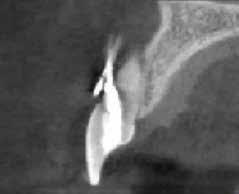

Egy 38 éves nőbeteg a korábban kezelt jobb felső második kisőrlőfogából (1.5) kiinduló mérsékelt fájdalom miatt jelentkezett rendelésünkön. A kórtörténetében jelen panasza szempontjából releváns információ nem szerepelt. A beteg a klinikai vizsgálat során vertikális kopogtatásra enyhe érzékenységet jelzett. A kérdéses fog körül mérhető szondázási mélység és a fogmobilitás fiziológiás volt. Periapicalis röntgenfelvételen egy, a fog gyökércsúcsán túl presszálódott betört gyökérkezelő műszerből származó eszközfragmentumot láttunk (2. a. ábra). A preoperatív CBCT-felvétel a buccalis csontlemez épségét igazolta (2. b-c. ábra). A fog revíziója öt hónappal korábban történt. A már előzőleg gyökérkezelt, gyökértömött, majd revideált 1.5-ös fog esetében a diagnózisunk periodontitis periapicalis symptomatica volt. A periapikális elváltozás kezelése érdekében navigált endodonciai mikrosebészeti beavatkozást végeztünk.

a-m. ábrák: Preoperatív röntgenfelvétel (a) és preoperatív CBCT-felvétel a jobb felső 5-ös (1.5) fogról, sagittalis (b) és axialis (c) nézetek. Az intraorális szkennelés során kapott STL-fájl (d). A 1.5-ös fog navigált endodonciai mikrosebészeti beavatkozásához tervezett sablon (e). A 1.5-ös fog navigált endodonciai mikrosebészeti beavatkozásához nyomtatott sablon (f). Teljes vastagságú mucoperiostealis lebenyt emeltünk (g). A sablont a helyére illesztettük, és a csontablak határait jelöltük (h). A fog gyökerén kívül eső, betört eszköz a 1.5-ös fog periapicalis régiójában (i). Az eltávolított betört eszköz (j). A rezekció, retrográd preparáció és a TotalFill BC RRM Fast Set Putty anyaggal elkészített retrográd gyökértömés utáni röntgenfelvétel (k). A lebenyt varratokkal rögzítettük (l). A kétéves kontroll során készített röntgenfelvétel (m).

gítségével tovább módosítottuk. Az így kapott sebészi sablon egyértelműen meghatározta a periapikális terület eléréséhez szükséges csontablak határait (2. e-f. ábra) Helyi érzéstelenítést követően teljes vastagságú mucoperiostealis lebenyt képeztünk, majd a buccalis csont feltárását követően (2. g. ábra) a sablon segítségével bejelöltük a preparálandó csontablak határait (2. h. ábra). A csontablak kialakítása során Piezotome CUBE LED kézi-darabot alkalmaztunk, majd a leemelését követően a betört eszközt megkerestük (2. i. ábra) és eltávolítottuk (2. j. ábra). A rezekciót ultrahangos megmunkáló fejekkel (ACTEON) végeztük, majd retrográd preparáció következett.

A retrográd gyökértömés elkészítése során TotalFill BC RRM Fast Set Putty-t (FKG) használtunk (2. k. ábra). A lebeny széleit 5/0-s Prolene varratokkal egyesítettük (2. l. ábra). A varratok a műtétet követően 72 órával kerültek eltávolításra. A beteg két évvel később kontrollröntgen készítése céljából érkezett rendelőnkbe. A vizsgálat során a fog tünetmentesnek és funkcióképesnek bizonyult (2. m. ábra).